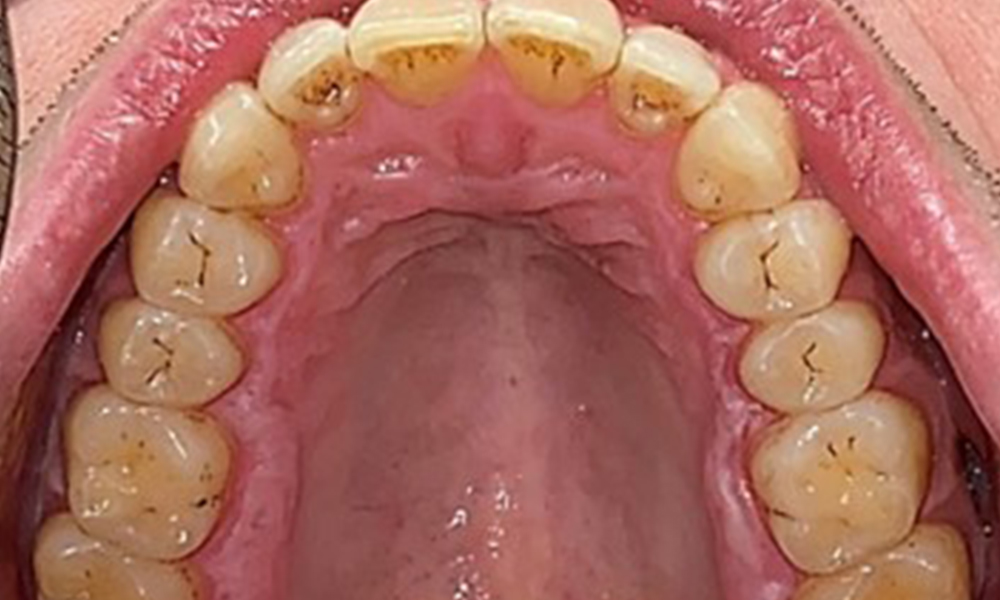

Il n'y a pas eu de résultats pathologiques extra-oraux. Lors de l'examen intrabuccal, l'inspection de la vue frontale a révélé une décoloration brunâtre près de la gencive kératinisée et à la transition vers la muqueuse mobile (Fig. 2), qui pourrait être attribuée à la consommation de nicotine. Des lésions blanchâtres de la muqueuse ont été observées sur le palais, en particulier près des surfaces palatines des molaires maxillaires, ce qui indique une kératinisation accrue et peut également être attribué à la consommation de nicotine. La langue était recouverte d'un enduit amovible blanc et brunâtre.

Le patient a une dentition complète avec un total de 28 dents. Il y avait des érosions et des attritions notables. (Fig. 4, Fig. 5). En raison du bruxisme, le patient a porté pendant de nombreuses années une attelle avec une gouttière ajustée la nuit. Les érosions ont été causées par une consommation prolongée de boissons isotoniques. Aucune perte d'os parodontal ou carie active n'a été observée.